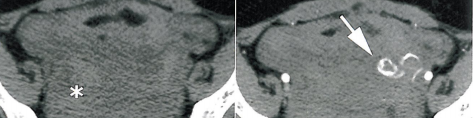

Il permet ainsi d'optimiser l'exploration de pathologies gynécologiques importantes, comme l'endométriose pelvienne ou la caractérisation des masses annexielles, qui restent la principale cause de chirurgie gynécologique (chapitres 4, 5, 6 et 7).

Enfin, l'échographie et la tomodensitométrie restent les examens de référence dans d'autres indications où l'IRM pourrait également avoir une place plus importante dans le futur.

Il s'agit de l'évaluation de la carcinomatose péritonéale (chapitre 11), de l'exploration des douleurs aiguës d'origine gynécologique (chapitre 12), de l'exploration de l'infertilité féminine (chapitre 13), les infections génitales de haut niveau (chapitre 14), ainsi que l'investigation des problèmes de stature pelvienne (chapitre 15).